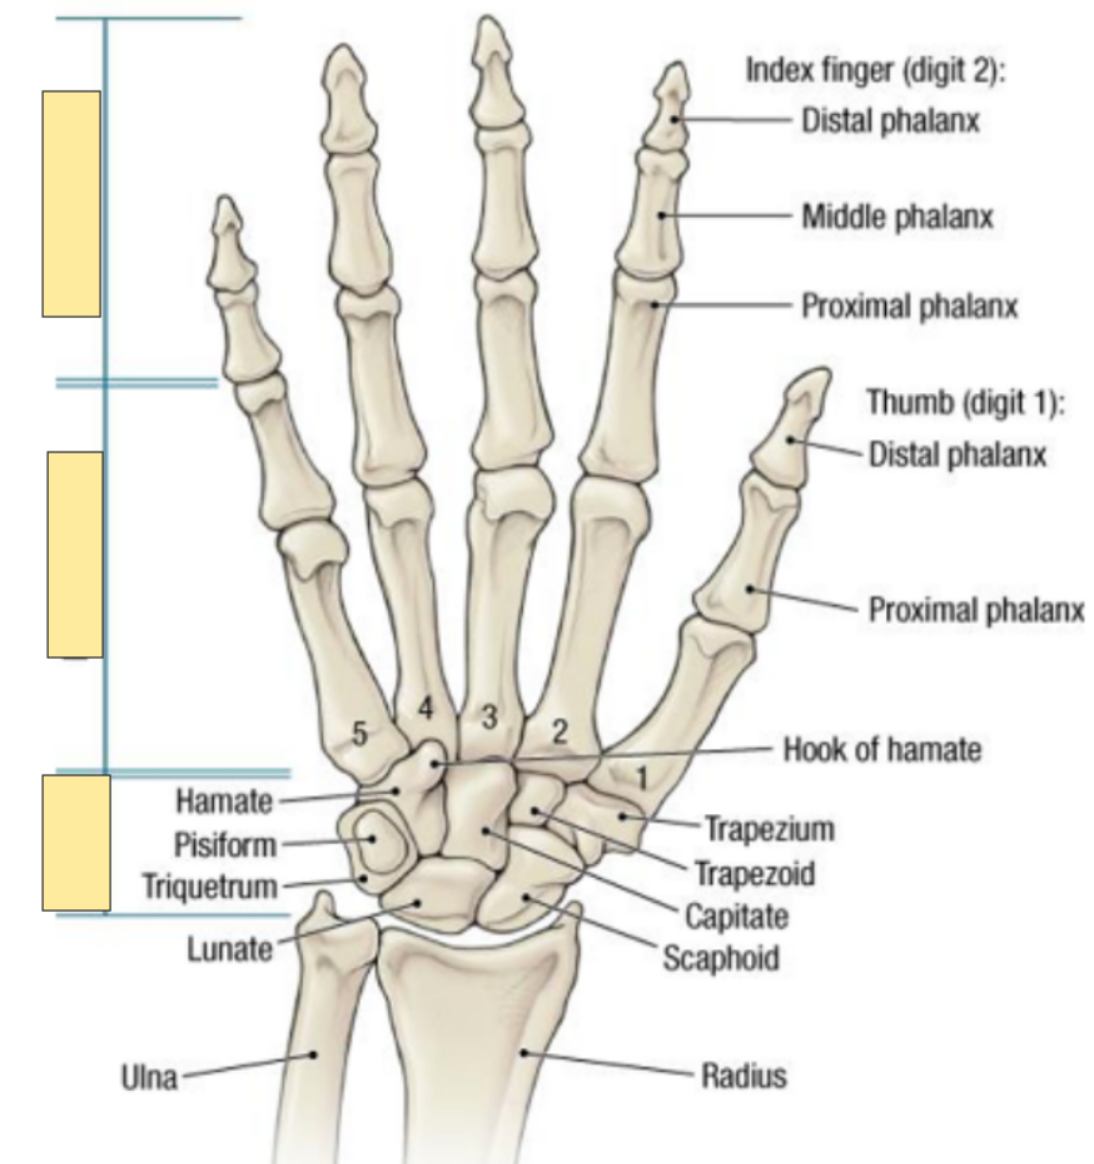

what are the three parts of the hand?

phalanges

metacarpals

carpals

What are the 3 divisions of the phalanges?

proximal, middle and distal

What are the fingers called? thumb?

digits and the thumb is called the pollex